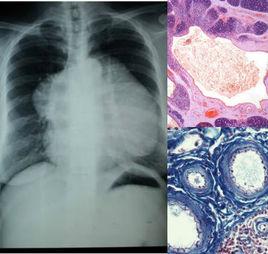

大多為先天性,系胸舌咽管、胸腺導管或腮裂的殘餘,少數為後天性,由炎症或Hassall小體的囊性新生物演變而成。好發於頸部胸鎖乳突肌前緣深部,其次為縱隔。一般無自覺症狀。囊腫呈圓形或橢圓形,直徑1~17 cm,可推動,無壓痛。少數患者有吞咽疼痛、吞咽困難、呼吸疼痛和脊柱麻痹。

根據臨床好發部位及無痛性囊腫,其中病理組織內囊壁見殘餘的胸腺組織和特徵性Hassall小體及膽固醇結晶可以診斷。需與腮裂囊腫、囊腫性胸腺瘤、鱗癌的淋巴結轉移等鑑別。